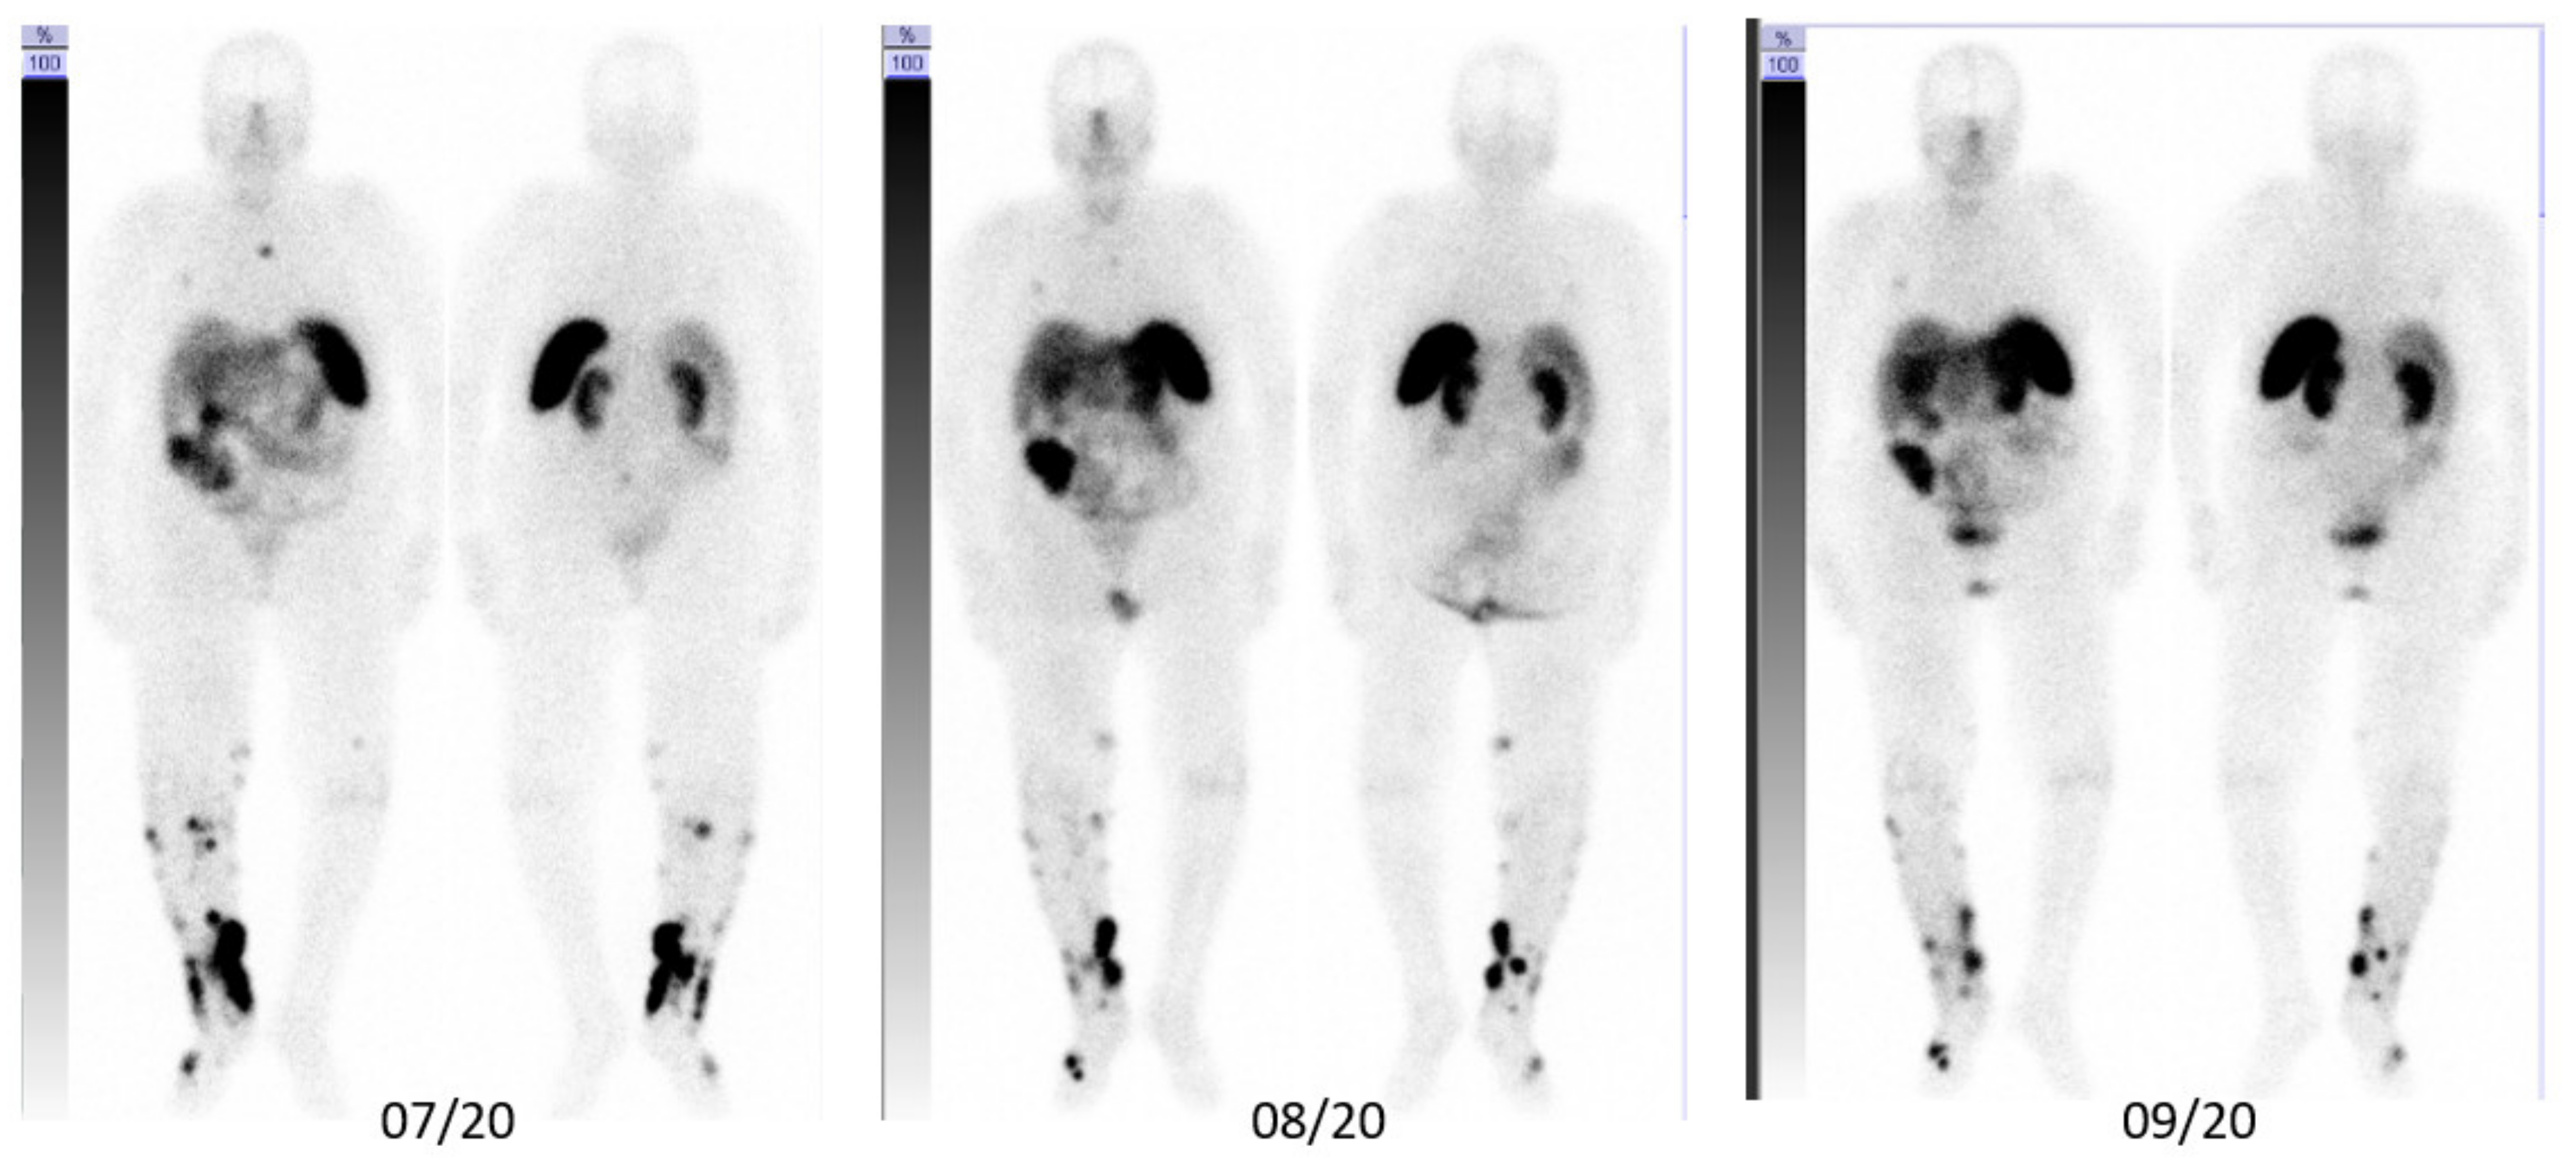

3. Case Description